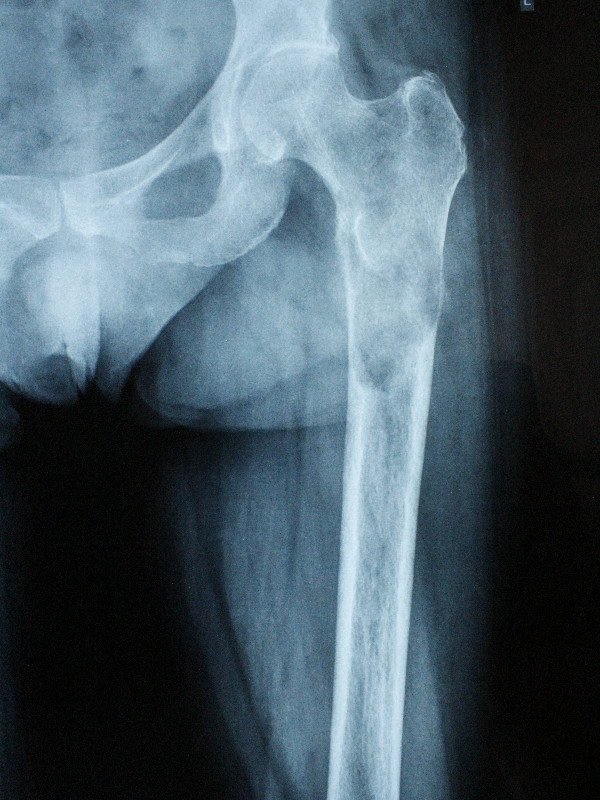

1. Солитарная плазмоцитома верхней трети бедренной кости.

После хирургического лечения в одной из зарубежных клиник по поводу перелома бедренной кости, как впоследствии оказалось, вторичного характера, 40-летний пациент обратился в МЦ ''Наири''.

В ходе обследования была диагностирована солитарная плазмоцитома.

После проведения предоперационной химиотерапии пациент был прооперирован – была произведена сегментарная резекция верхней трети бедренной кости, образовавшийся дефект был замещен индивидуальным биполярным эндопротезом бедренной кости и тазобедренного состава, изготовленным на заказ в Европе. В результате проведения органосохранного лечения удалось сохранить функционирующую конечность пациента.

До операции